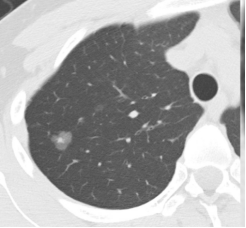

纯磨玻璃结节(类似荔枝果肉)、混合磨玻璃结节(类似荔枝果肉与果核并存)(恶性风险较高)、实性结节(类似荔枝果核)。

纯磨玻璃结节 | 混合磨玻璃结节 | 实性结节 |